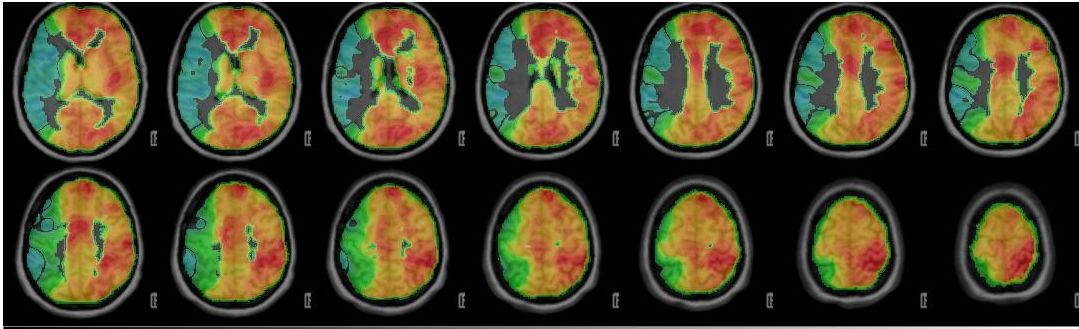

Wissenschaftliche Abbildung

PET/CT mit Darstellung der einseitig reduzierten Reservekapazität/Durchblutung (kalte Farben) im Vergleich zum physiologischen Anstieg der Perfusion auf der Gegenseite (warme Farben).

PET-CT nach Diamox Gabe

PET-CT nach Diamox Gabe zeigt eine einseitig deutlich reduzierte Perfusionsreserve (grüne Farben) im Vergleich zur Gegenseite mit ausreichendem Anstieg der Durchblutung (warme Farben).